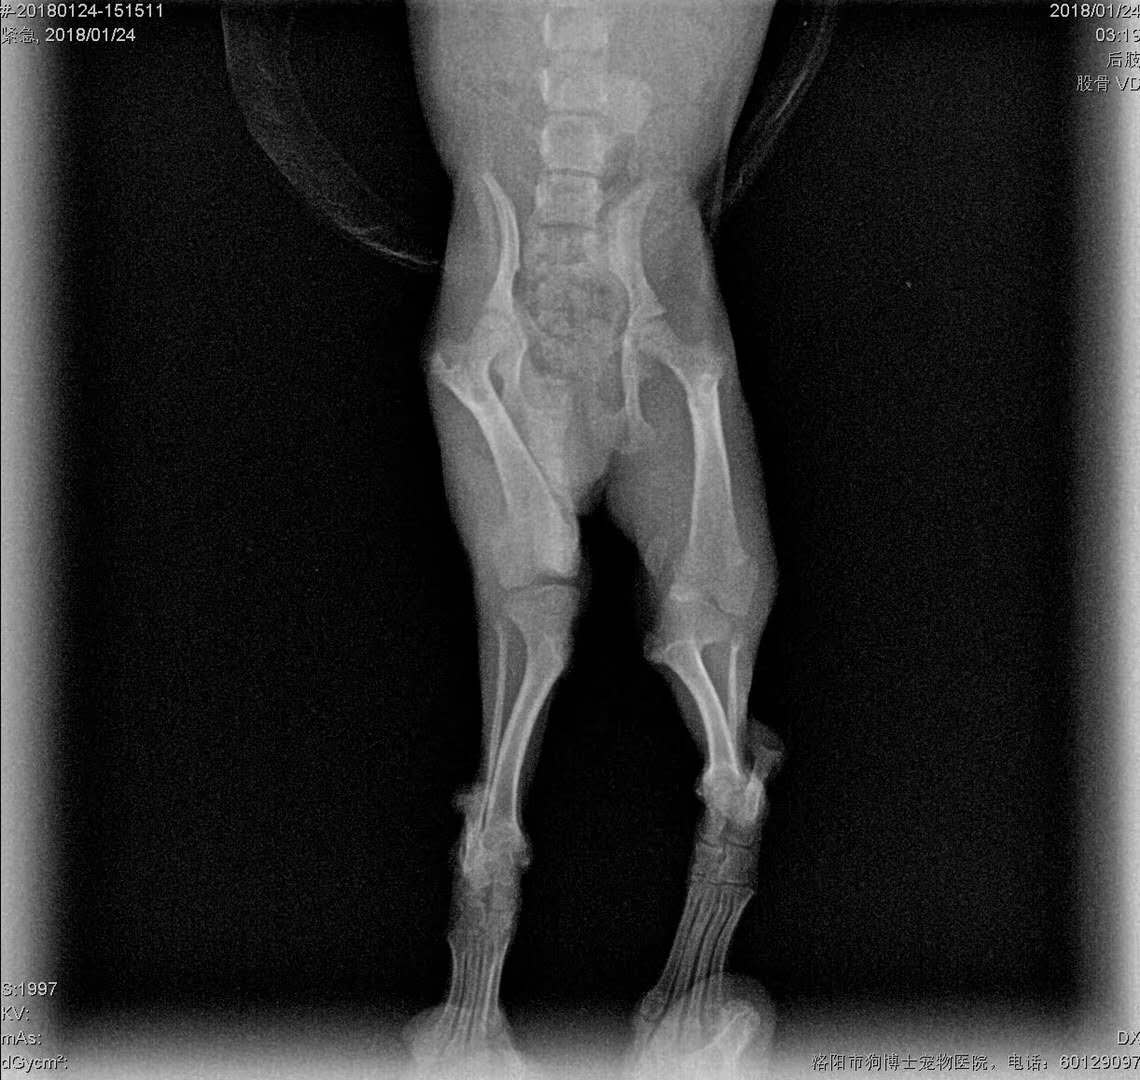

微小泰迪髕骨移位手術(shù)再一例:微小體泰迪,雙側(cè)髕骨移位,其中左腿嚴重,為4級移位,走路時難以負重,來院實施滑車溝再造術(shù)、脛骨粗隆移位術(shù)、及髕骨周圍軟組織修復術(shù)。手術(shù)順利,狗狗很頑強,麻醉剛剛蘇醒,走路姿勢就恢復正常了,見倒數(shù)第三張圖,住院護理中。